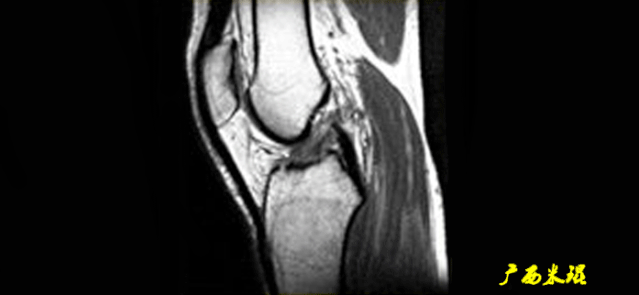

3)方向异常(ACL 下垂征):

有较完整的韧带低信号,但方向异常,呈下垂状。

一般见于股骨附着部的陈旧损伤,损伤的ACL下垂并粘附在PCL上。